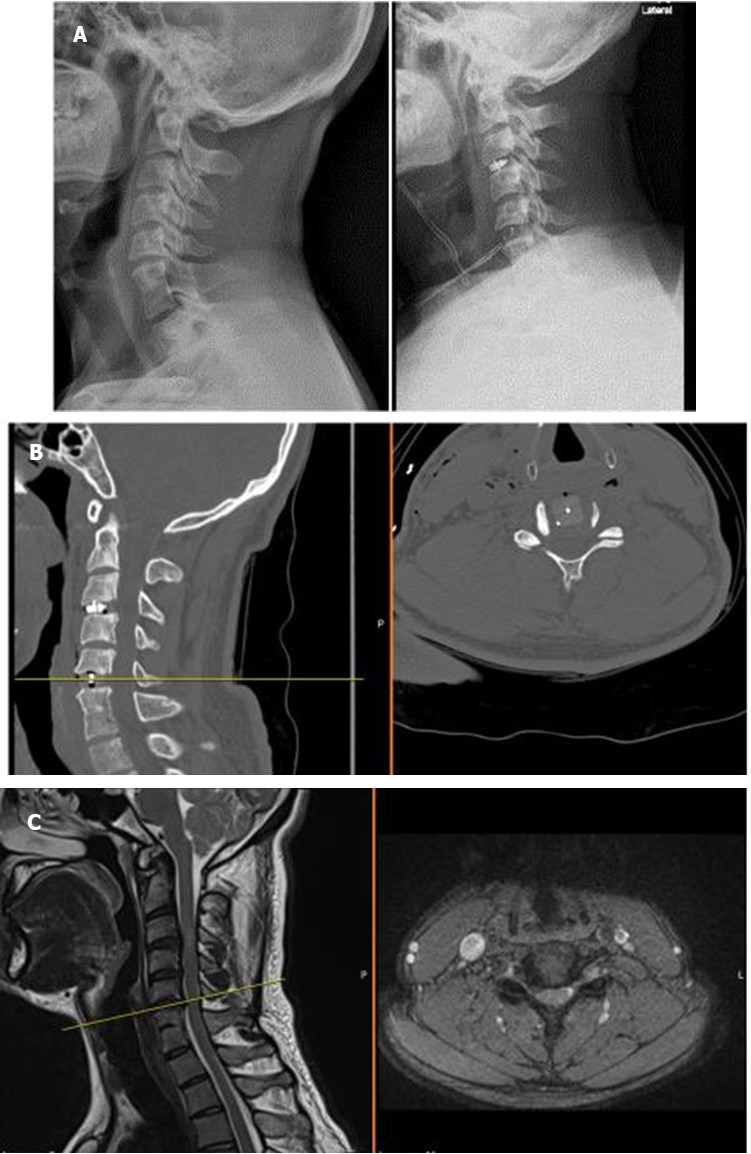

Figure 1A, B, C.X-ray, computerized tomography, and magnetic resonance imaging views of a Yilmaz-Yucesoy Classification System Grade 2 patient.

X-ray, computerized tomography, and magnetic resonance              imaging views of a Yilmaz-Yucesoy Classification System Grade 2 patient.